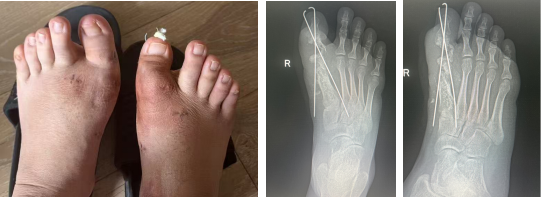

二期右足行3D打印个体化跖趾关节重建方案:通过CT获取足部三维数据,1:1还原骨骼缺损与畸形结构,数字化设计完全匹配患者解剖的定制假体,再通过金属3D打印技术制造专属假体,真正实现“量骨定制、精准植入”。

定制假体

手术过程顺利,术中定制假体与骨床完美贴合,畸形彻底矫正。术后患者关节活动保留,步态恢复理想,康复进程显著快于传统手术。